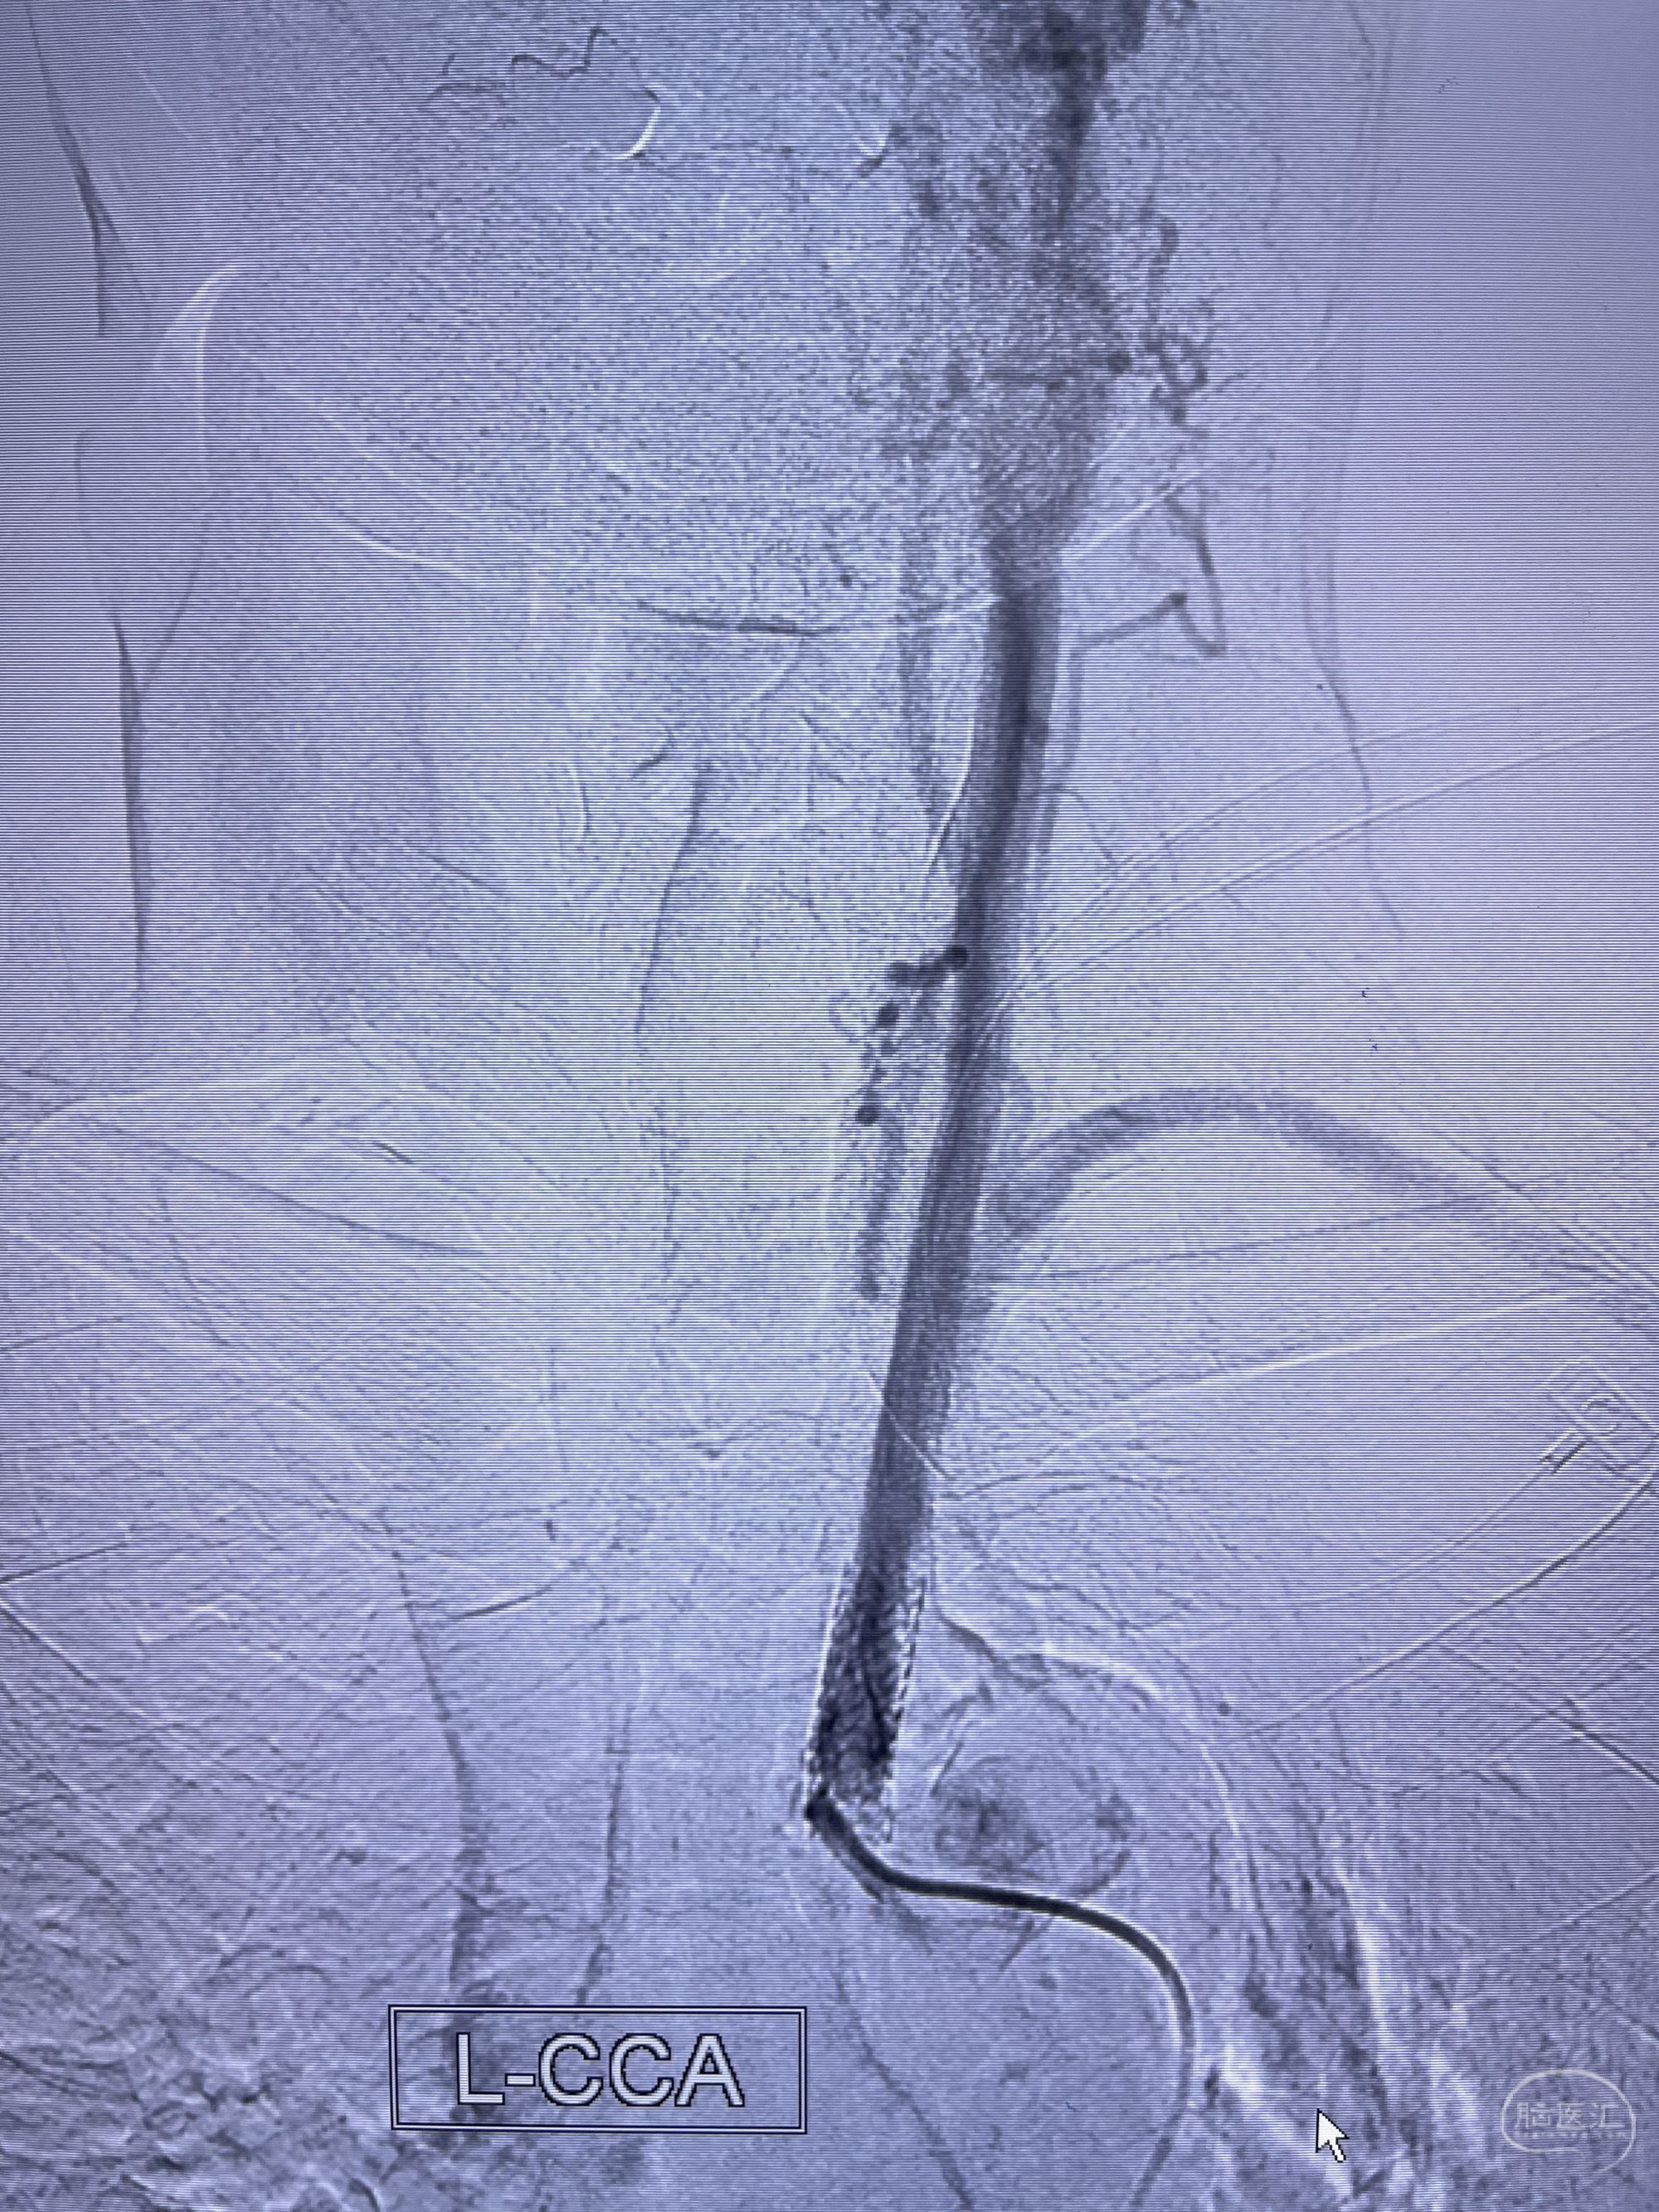

脑血管造影2023.03.06:右侧颈内动脉颈段至岩骨段闭塞,可见后后循环通过原始三叉动脉吻合代偿至海绵窦段,后交通区可见囊状造影剂填充影,左侧锁骨下动脉呈“残端”改变,呈“右侧颈总动脉支架成形术后改变”,支架内血流通畅,可见后交通吻合显影至左侧大脑后动脉,并可见左枕动脉吻合椎动脉至锁骨下动脉

2023-03-06DSA:

1.右侧颈内动脉及左侧锁骨下动脉闭塞

5.左侧颈总动脉起始部支架术后

6.左侧颈外动脉可见吻合显影至左侧椎动脉并逆行供血至左侧腋动脉

7.左侧锁骨下动脉闭塞

1.箭头处为右侧颈内动脉后交通动脉处重度狭窄,狭窄前壁为不规则动脉瘤;

2.狭窄远端颈内动脉由左侧颈内动脉经左侧后交通动脉—基底动脉顶—右侧后交通—右侧颈内动脉—右侧大脑中动脉途径代偿

左侧颈内动脉经左侧后交通动脉—基底动脉顶—右侧后交通—右侧颈内动脉—右侧大脑中动脉途径代偿

左侧颈外动脉经脑膜支吻合至左侧椎动脉—左侧锁骨下动脉—左侧上肢